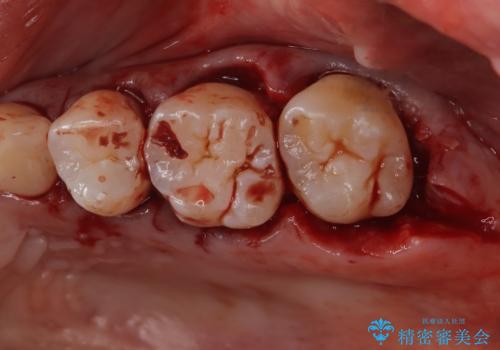

- 定期的にクリーニング(保険適応)に通って頂いている患者さんです。歯周ポケットが4ミリあったため歯茎を開いて歯石を除去するためにオープンフラップ術を行うことにしました。

歯周ポケットがそれほど深くない患者さんでしたが、いざ歯茎を開いてみるとそこにはたくさんの歯石がありました。もし歯周ポケットが4ミリだからと言って放置していれば数年後には、沢山の骨が無くなっていたことが予期出来ます。現段階で歯茎の下にある歯石を除去することにより骨が無くなることを予防する事が出来ました。